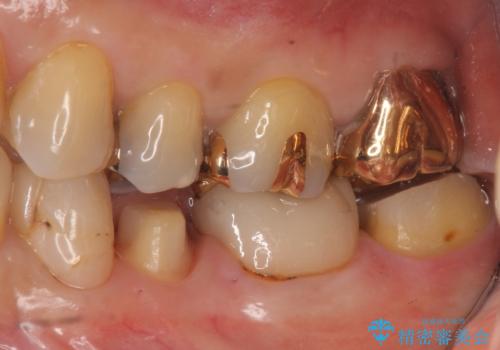

昔いれたクラウンが割れたので金属の被せ物を入れたい

1. 開始前

2. 治療途中

3. 終了時